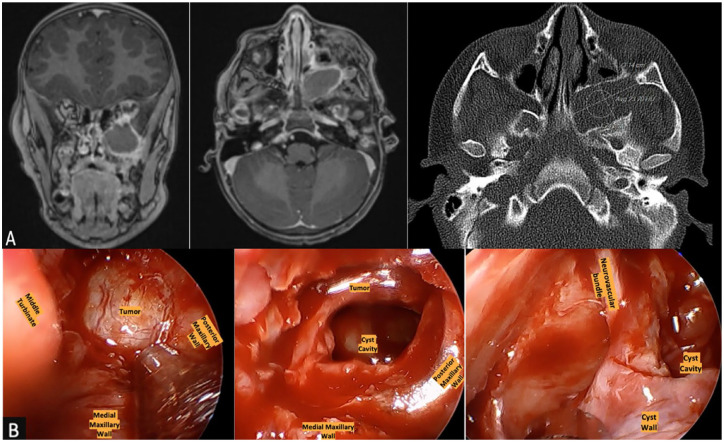

Infratemporal fossa (ITF) tumors are rare in children and may present with a variety of symptoms. Teratomas are neoplasms derived from the 3 germ layers and approximately 6% to 10% are within the head and neck. Our study discusses one of the first reported cases of teratoma in the ITF in a pediatric patient. A 3-year-old girl presents with 2 years of recurrent monthly left periorbital swelling accompanied by fevers, skin discoloration, and pain. Prior episodes were treated with antibiotics with incomplete resolution. Imaging revealed a cystic lesion centered in the ITF. She was taken for endoscopic endonasal biopsy of the lesion and had no complications. Pathology revealed a mature teratoma composed primarily of pancreatic tissue. Providers should consider masses such as teratoma in the differential for ITF tumors and periorbital edema unresponsive to typical treatment.